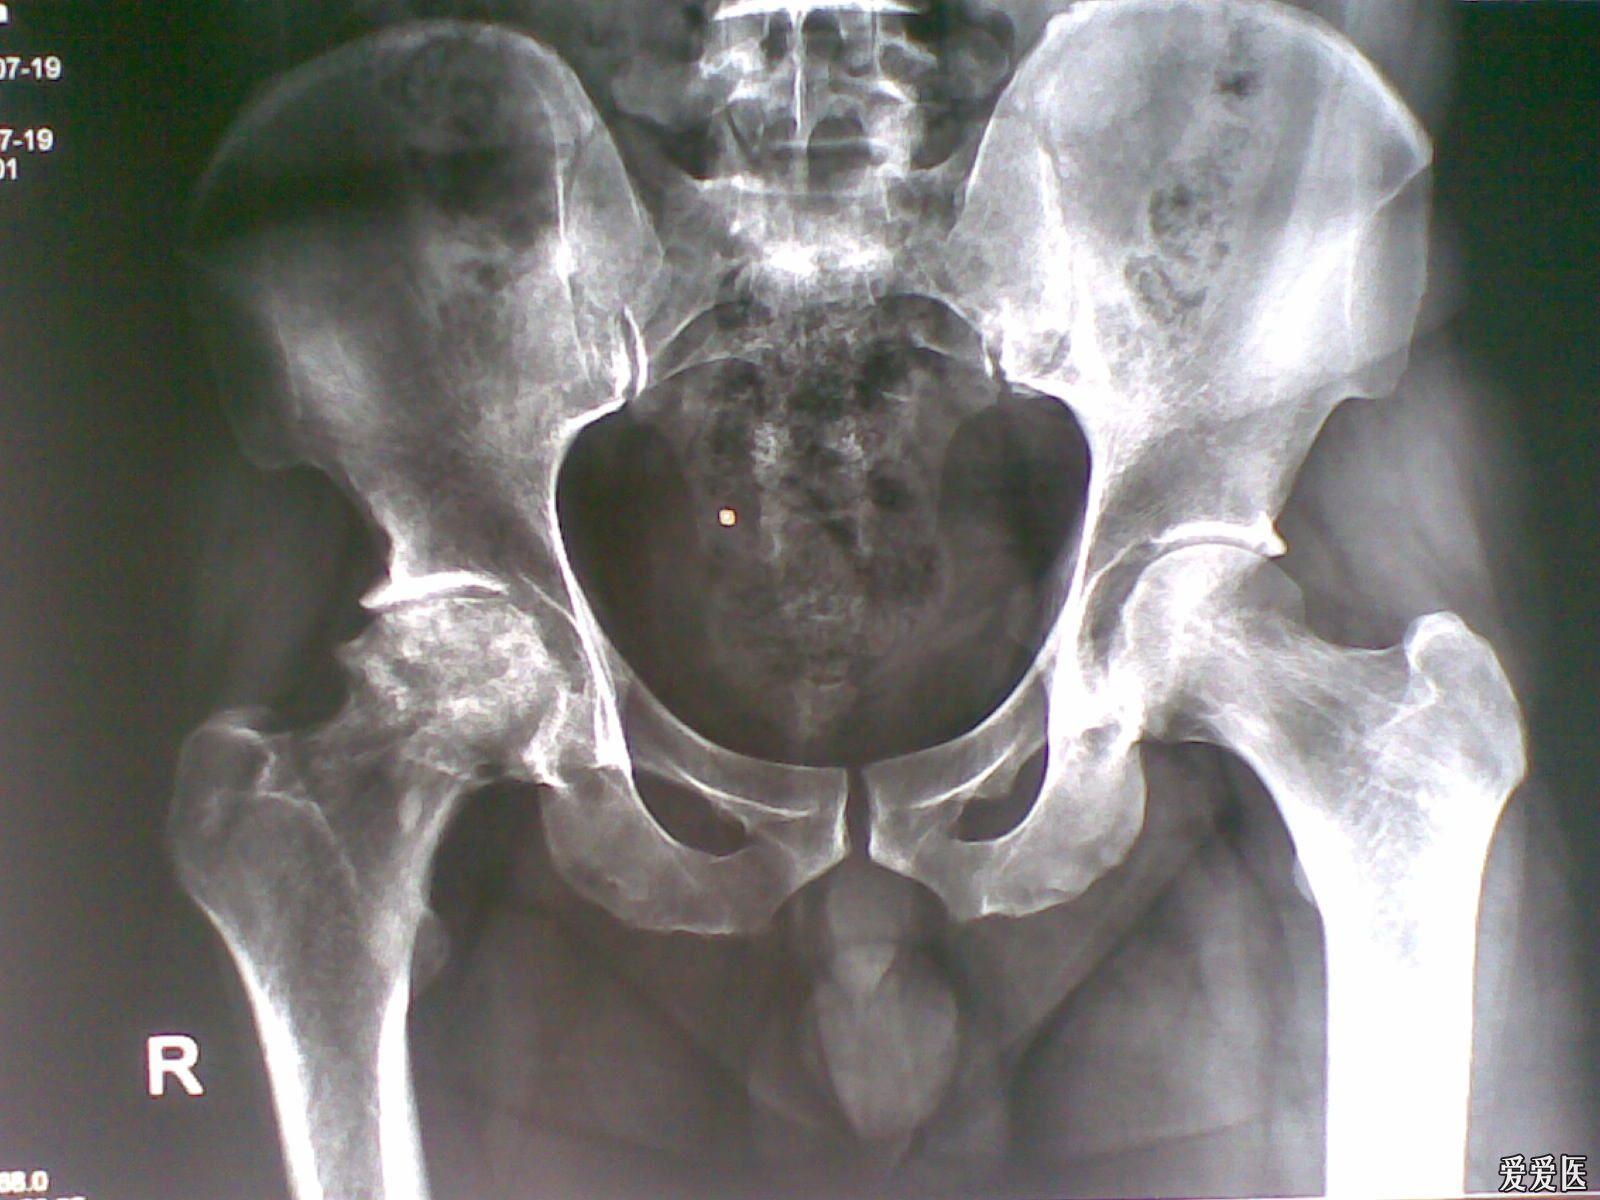

股骨头坏死(ONFH)又称缺血性股骨头坏死,是骨科中常见的难治性疾病,主要病因是股骨头血液供应遭到破坏,导致骨髓成分减少与骨细胞死亡,最终股骨头坏死塌陷,引起髋部疼痛,降低患者的生活质量。

股骨头坏死可发生在任何年龄段,我国股骨头坏死的发病率高且逐年升高。据2017年我国统计的数据显示,我国15岁及以上的普通人群中约812万人患有非创伤性骨头缺血坏死。多数患者在早中期没有采取积极措施,导致病情发展至末期,难以治疗。